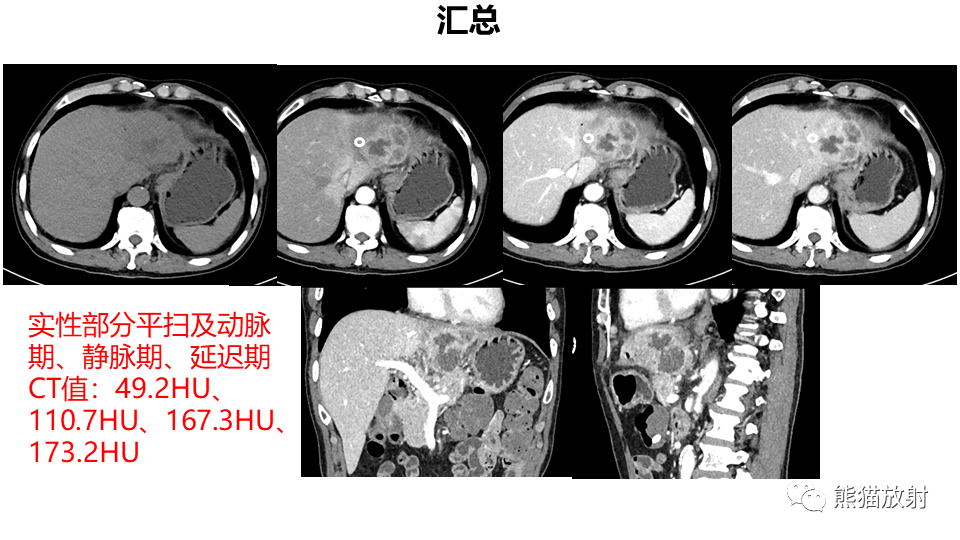

【PPT】肝内胆管细胞癌 VS 肝脓肿